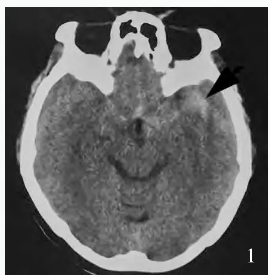

颅内多发动脉瘤长期随访一例

病例

2025-10-02